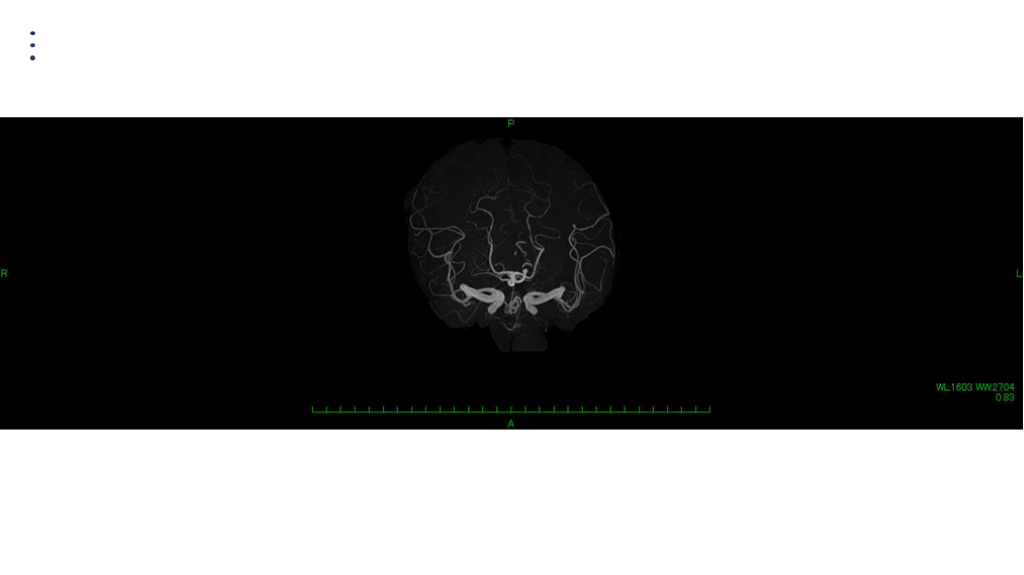

画像 所見 DAY 30 MRA 改善